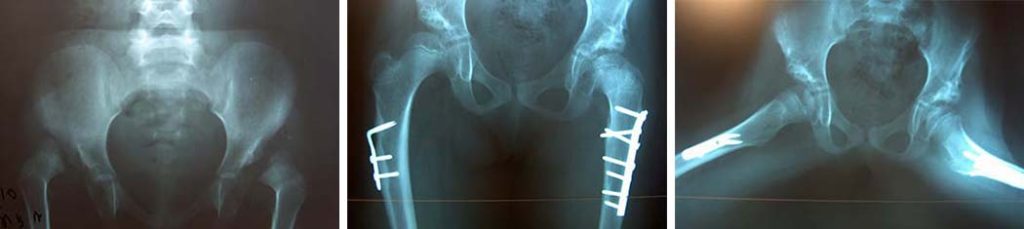

Κλινική εικόνα εξαρθρήματος αριστερού ισχίου με βράχυνση και περιορισμό απαγωγής σε αγόρι. Ακτινολογική εικόνα και εικόνα μετά την ανοικτή ανάταξη με συνοδό οστεοτομία πυέλου.

Η επέμβαση αυτή είναι εξαιρετικά δύσκολη, απαιτεί εμπειρία, σε περιοχή όπου σε μικρό χώρο, υπάρχει διαταραχή στην ανατομία και η προσέγγιση στην αληθή κοτύλη έχει δυσκολίες.

Στην συνέχεια γίνεται ακινητοποίηση του ισχίου σε γύψινο επίδεσμο hip spica για διάστημα 6- 8 εβδομάδων και ακολουθεί προφύλαξη με κηδεμόνες για χρόνο που απαιτείται για την κατάλληλη κάλυψη της κεφαλής από το οστικό χείλος της κοτύλης.

Ακτινολογική εικόνα υψηλού εξαρθρήματος ισχίου σε νήπιο 3 ετών και αντιμετώπιση με ανοικτή ανάταξη και οστεοτομία μηρού και πυέλου.